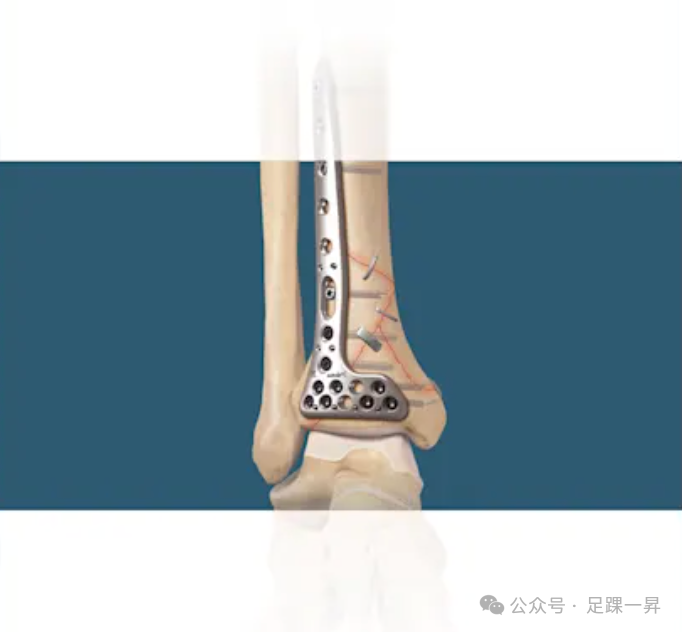

所有手术均在全身麻醉下进行。患者采用仰卧位,取踝关节外侧入路。首先在外踝骨折线近端和远端之间做皮肤切口。皮肤切口一般为3cm左右,并根据需要延长切口。暴露骨折端后直视下使用持骨钳复位骨折端并维持复位,钻孔后在中心位置垂直于骨折线放置镍钛合金骑缝钉进行固定。用单枚骑缝钉固定后移除持骨钳,然后在骨折的后方和前方部位再放置两枚骑缝钉。术后,患者从手术当天起即可在踝关节支具保护下进行耐受范围内的负重。术后12周移除踝关节支具。所有患者术后均咨询物理治疗师进行运动治疗。

图示镍钛合金骑缝钉固定技术。A:初始踝关节外侧3cm左右皮肤切口;B:使用持骨钳复位骨折;C 和 D:钻孔后在骨折线中心垂直放置镍钛合金骑缝钉进行固定;E:单枚骑缝钉固定后移除持骨钳,在骨折后、前部位再放置两枚骑缝钉。